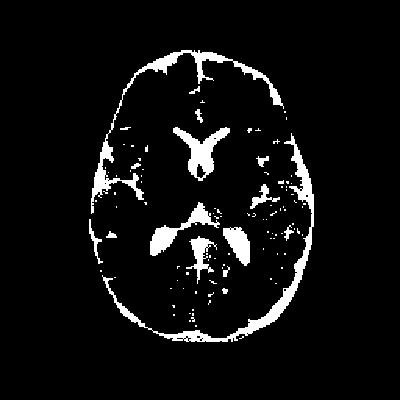

从代码中可以看出,我们首先加载了一个.mat格式的数据文件,其中包含了待处理的图像img和掩膜图像mask。掩膜图像的作用是指示图像中感兴趣区域的位置,从而帮助我们仅对目标区域进行分割,而忽略背景噪声。

- 掩膜图像:如图2所示,掩膜图像指示了图像中感兴趣区域的位置,从而帮助我们仅对目标区域进行分割。